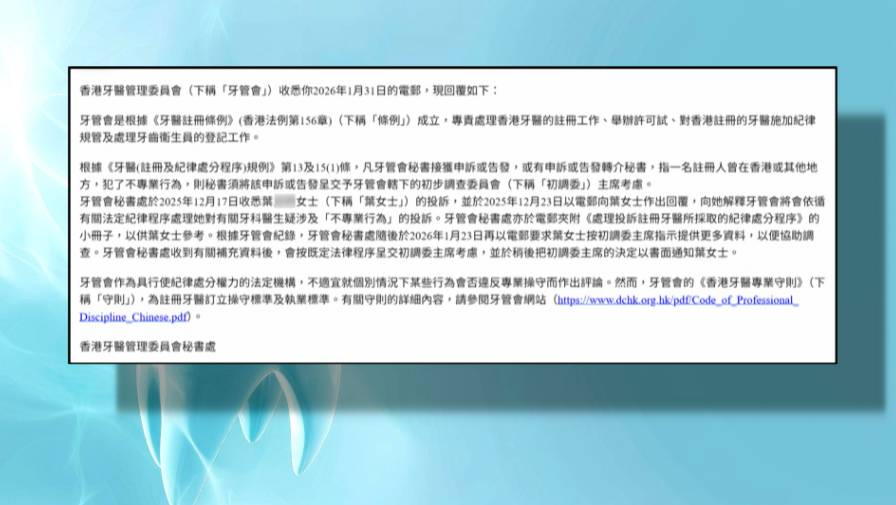

網民狠批黑心牙醫 質疑醫生無牌執業